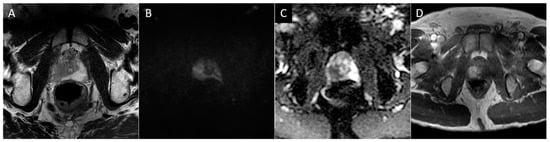

Figure 2. Axial T2 (A), diffusion-weighted b2000 (B), apparent diffusion coefficient (C), and dynamic contrast-enhanced (D) images of the pelvis demonstrating a focal ill-defined T2 hypointense lesion in the right midgland posterolateral peripheral zone with corresponding diffusion restriction and asymmetric enhancement, characterized as PI-RADS 5 per PI-RADS v2.1.

To briefly summarize the system, PI-RADS uses a grading scale from 1 to 5, wherein benign-appearing lesions receive a score of 1, and highly suspicious lesions are given a score of 5. The peripheral zone of the prostate is primarily assessed using diffusion-weighted sequences (DWI/ADC), where more convincing diffusion restriction is considered increasingly suspicious. In contrast, the transition zone is primarily assessed using T2-weighted sequences, where hypointense lesions are considered more suspicious as they become less circumscribed, homogenous, and with obscured margins, leading to suspicious lesions often being likened to “smudged charcoal” [28]. In both peripheral and transition zone lesions, maximal lesion diameter determines if a suspicious lesion is categorized as 4 or 5. DCE only impacts the overall scoring of a lesion in situations where a positive DCE can upgrade a peripheral zone lesion from 3 to 4. PI-RARDS v2.1 clarifies that DCE is considered negative if enhancement is diffuse, multifocal, does not correlate to a T2 or DWI abnormality, or if it does correspond to lesions compatible with BPH (Figure 2) [27]. While PI-RADS is also used during the setting of active surveillance, the Prostate Cancer Radiological Estimation of Change in Sequential Evaluation (PRECISE) score has also been developed to help standardize reporting of active surveillance cases and better stratify those who need or can avoid surveillance biopsy [45]. The PRECISE score is based on a 5-point scale where a score of 1 indicates the resolution of suspicious MRI features, 2 indicates a reduction in volume/conspicuity of MRI features, 3 indicates a stable MRI appearance, and scores of 4 and 5 demonstrate a significant increase in volume/conspicuity and/or definite stage progression [45]. Using this standardized approach, this initial study found that PRECISE scores of 1–3 have high NPV and can reduce the need for re-biopsy during active surveillance, while scores of 4–5 have moderate PPV and should be closely monitored or biopsied [45].